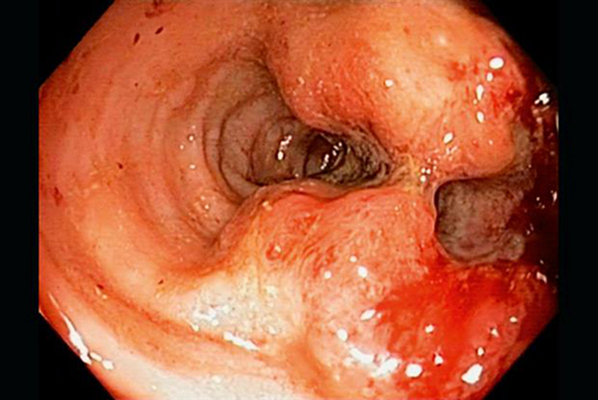

結腸癌症狀 (7)

結腸癌症狀 (8)

結腸癌症狀 (9)

結腸癌症狀 (49)

結腸癌症狀 (5)

結腸癌症狀 (50)

結腸癌症狀 (51)

結腸癌症狀 (6)